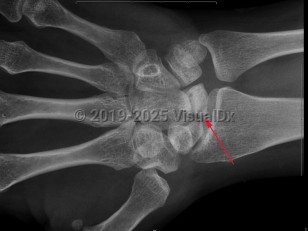

Avascular necrosis

Avascular necrosis (osteonecrosis) is characterized by tissue death due to reduction or loss of blood supply to a bone. Causes include joint or bone trauma, fatty deposits in blood vessels, corticosteroid use, alcohol abuse, and some diseases. Other risk factors are chemotherapy, radiation therapy, and organ transplantation. May occur at any age, but most commonly occurs in adults aged 30-60. Patients are typically asymptomatic early on, but most experience joint pain increasing in severity as the disease develops. The femoral head site is most commonly affected, but the humeral head site, femoral condyles, and small bones are also sites of common occurrence. Typically, clinical presentation consists of sudden onset of pain in the joint.

Related topics: avascular necrosis of knee, avascular necrosis of scaphoid, Köhler disease, osteonecrosis of the femoral heads, osteonecrosis of the humeral heads, progressive avascular necrosis of lunate